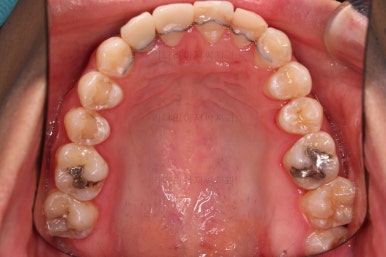

임플란트 완료시 모습인데요.

임플란트 식립부터 완료까지 시간이 걸리다보니 최종 종료까지는 총 19개월이 걸렸습니다.

교합도 잘 맞고 임플란트도 잘 완성되었네요.

매복치아도 손상 없이 잘 배열이 되었고, 교합도 좋게 마무리 되었습니다.